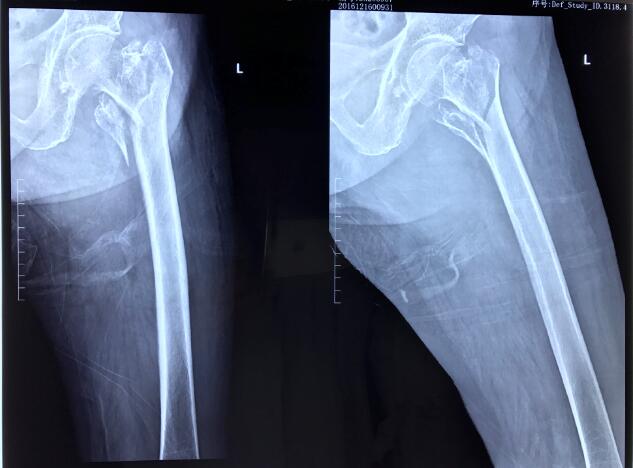

祖奶奶93岁高龄,因不慎摔伤致左侧股骨粗隆间骨折,伤后前往附近医院就诊。因患者高龄,合并糖尿病,手术风险极高,该院放弃治疗,转入我院关节与显微修复外科就诊,我科胡孔足主任术前结合患者综合情况,联合内科、麻醉科会诊,控制糖尿病,结合神经阻滞麻醉,采用股骨近端防旋髓内钉(PFNA)闭合复位内固定方案,以最小的创伤获得良好的固定。手术顺利,术后患者恢复良好。术后两天即可扶拐下地行走,迅速恢复生活自理能力。老年股骨粗隆间骨折由于内固定手术要求高,失败率较高,很多医院建议放弃内固定术,采用人关节置换术。但是人工关节置换术存在手术损伤大,术后容易脱位等问题,患者恢复仍然困难。相对于人工关节置换手术,闭合复位髓内内固定具有创伤小,出血少,对髋部肌群未造成明显干扰的特点,降低了感染风险,避免了人工关节脱位、人工关节翻修等棘手问题,经过康复训练后可以很好恢复功能。